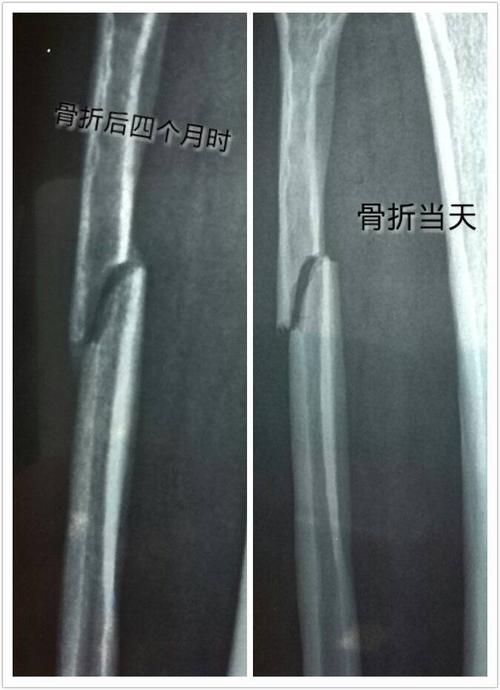

骨折四个月了,骨头还没愈合,有没有必要动手术上钢板